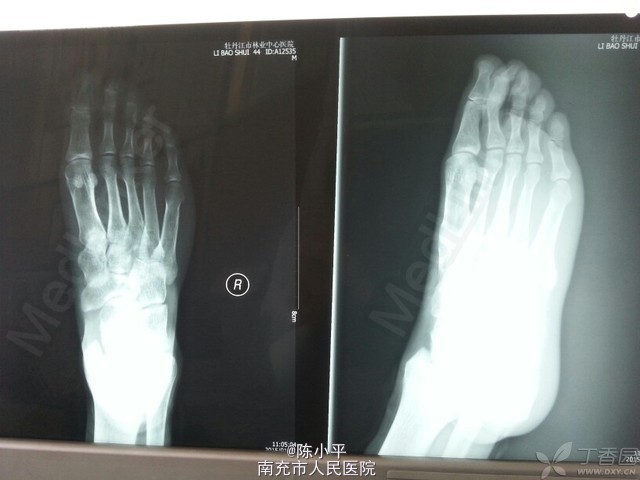

先天性左足多趾畸形

患者男性,23岁,先天左足多趾畸形,其它未见异常。